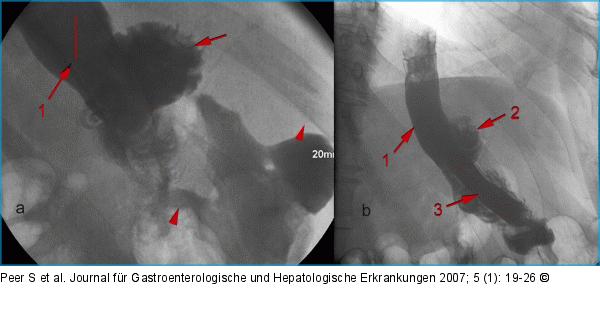

Abbildung 14: Magenbypass Zustand nach Magenbypass mit Anastomosenleck: a) Zustand nach Anlage eines ersten Stents (1) zur Überdeckung des Lecks, jedoch persistierender, massiver Kontrastmittelaustritt an der gastrojejunalen Anastomose (Pfeilspitze), mit Ausbreitung in den linken Oberbauch; b) überlappende Anlage eines 2. Stents (3) mit nun komplett abgedecktem Leck und unbehinderter Passage. Blindes Ende der Roux-Schlinge (2). |

Zustand nach Magenbypass mit Anastomosenleck: a) Zustand nach Anlage eines ersten Stents (1) zur Überdeckung des Lecks, jedoch persistierender, massiver Kontrastmittelaustritt an der gastrojejunalen Anastomose (Pfeilspitze), mit Ausbreitung in den linken Oberbauch; b) überlappende Anlage eines 2. Stents (3) mit nun komplett abgedecktem Leck und unbehinderter Passage. Blindes Ende der Roux-Schlinge (2). |